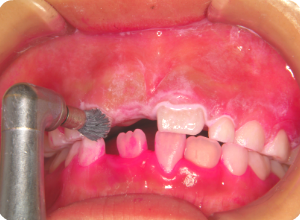

②磨き残しや汚れなどを、ブラシとラバーカップを使って落としていきます。